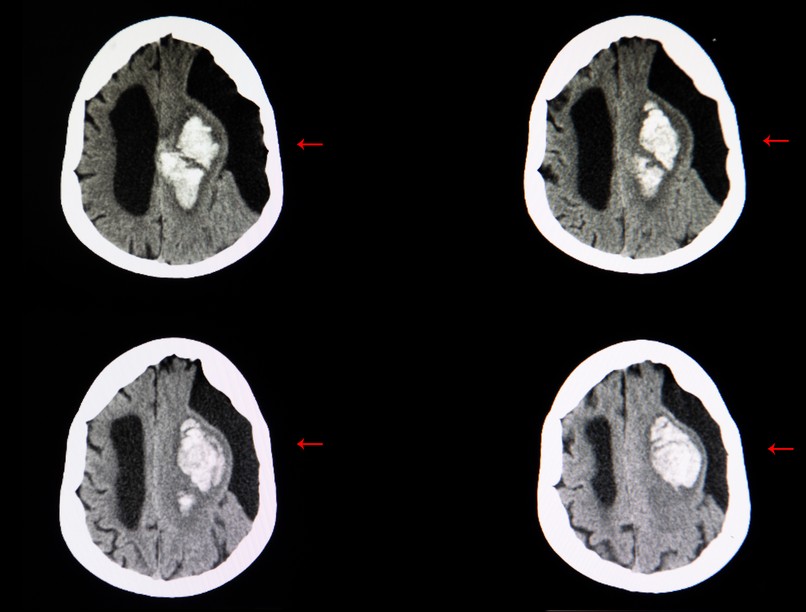

A subarachnoideális ciszta diagnózisa

A kis ciszták általában nem okoznak tüneteket és csak véletlenül kerülnek felfedezésre. A tünetek során felmerülő gyanú esetén MR (mágneses rezonancia) képalkotó vizsgálattal lehet a subarachnoideális ciszta meglétét igazolni.

Mivel a subarachnoideális ciszták megjelenése képalkotón több más struktúrára hasonlíthat, fontos a gondos radiológiai értékelés. Gyakran összetéveszthetők lehetnek tágult agykamrákkal, agyi atrófiával járó liquor-térfogat növekedéssel, vagy akár más folyadékkal telt elváltozásokkal, például epidermoid vagy dermoid cisztákkal. A korszerű MR-vizsgálat azonban kiválóan alkalmas a pontos meghatározásra: a ciszta jelintenzitása az agy-gerincvelői folyadékkal megegyező, a falai vékonyak, és érdemi kontrasztanyag-halmozást nem mutatnak.